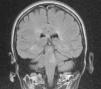

A magnetic resonance imaging was performed showing demyelinated plaques on the pons and hyperintense lesions located in the periventricular white matter and several subcortical e infratentorial injuries (Fig. 2).

The magnetic resonance subsequently confirmed the diagnosis and corroborated the clinical localization. The lesion in this patient involves the abducens nucleus on the right and may be components of the medial longitudinal fasciculus.